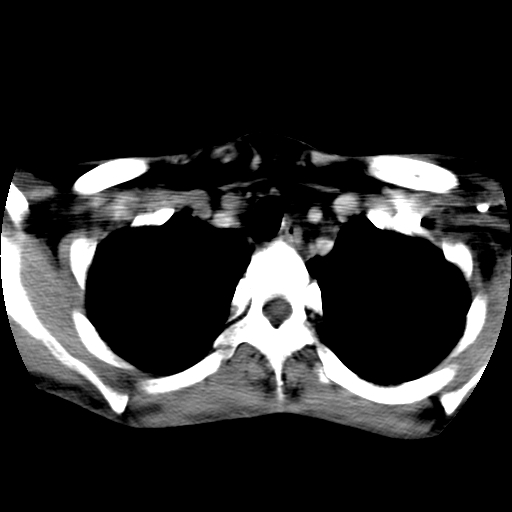

标题: CT24019:男,45岁,发现颈部肿物5个月。 [打印本页]

男,45岁,发现颈部肿物5个月,彩超示:双侧颈部及下颌部软组织增厚。

考虑双侧颈项部良性对称性脂肪增多症。